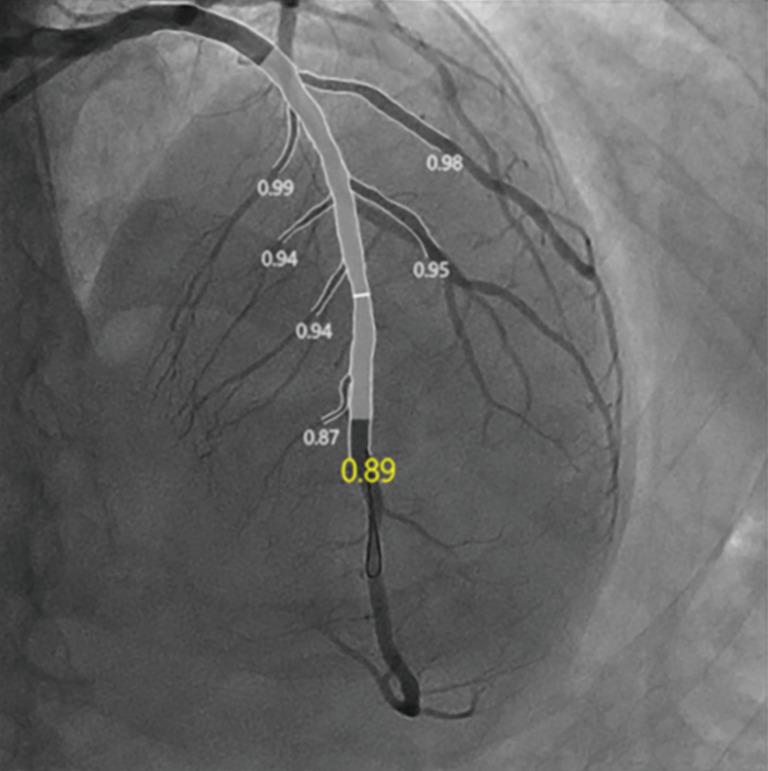

The data used in this prospective cohort research came from a prior multicenter prospective cohort study (ChiCTR1800019923). One hundred and thirteen consecutive STEMI patients were involved in our cohort study. Patients with STEMI who received primary percutaneous coronary intervention (pPCI) within 24 hours of symptom onset were included in the study and divided into two groups according to plaque characteristics derived from intravascular ultrasound (IVUS): a PR group and a non-PR group. The primary outcome was the incidence of no reflow or slow flow, the secondary outcome was major adverse cardiac events (MACEs) at 1-year follow-up.

This study enrolled 113 consecutive patients with STEMI [mean age 56 (range, 49-65.5) years; males 90.27%]. Of the 113 patients, PR was found in 93 (82.3%), while non-PR was found in 20 (17.7%). The PR group had a higher rates of plaque eccentricity index (64.28%±22.69% . 60.08%±15.54%; P=0.045), higher rates of lipid pool-like images (62.37% . 30.00%; P=0.008), and higher rates of tissue prolapse (22.95% . 13.33%; P=0.01). Compared with that in the non-PR group, the incidence of no reflow or slow flow was higher in the PR group after pPCI (26.88% . 5.00%; P=0.04). Multivariable logistic regression showed that PR [odds ratio (OR) =8.188; 95% confidence interval (CI): 1.020-65.734; P=0.048] was an independent predictor of no reflow or slow flow. Survival analysis revealed no significant differences in MACE incidence between the two groups at 1-year follow-up (7.61% . 10.00%; P=0.66). Furthermore, 29 patients with PR were treated without stenting, most of them were free of MACEs (27/29). MACE between subgroups of stenting and non-stenting had no significant differences (7.94% . 6.90%; P=0.86) in the PR group.